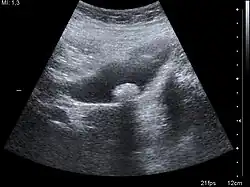

Ein Binnenecho bezeichnet in der medizinischen Ultraschalldiagnostik Muster unterschiedlicher Echogenität innerhalb einer anatomischen oder pathologischen Struktur, die durch unterschiedliche Reflexionen verschiedener Gewebearten entstehen. Die Analyse von Binnenechos ist ein wichtiges diagnostisches Werkzeug in der medizinischen Bildgebung.[1] Am häufigsten wird der Begriff für Muster innerhalb einer sonst echofreien Struktur, also flüssigkeitsgefüllten Gebilden wie Zysten und Hohlorganen, verwendet.[2] Abweichungen von der normalen Echogenität können dabei ein ganzes Organ betreffen und werden als schwach, stark oder fehlend eingestuft. Sie können aber auch nur in einem Herd (unifokal) oder in vielen Herden (multifokal) auftreten. Letztere gehen dann häufig in das normale Bild eines Organs über, man spricht dann von einem inhomogenen Binnenecho.[3]

Es handelt sich um ein Ultraschallecho aus dem Zentrum bestimmter Gewebe. Gelegentlich wird der Begriff auch für Echos innerhalb der Herzhöhlen und von Gefäßen angewandt. Zusätzlich wird aber auch manchmal bei Echos innerhalb eines Hohlraums (zum Beispiel der Gebärmutter) oder in sonst homogen soliden Strukturen von Binnenechos gesprochen.[2]

Binnenechos sind Hinweise auf die Struktur des Befundes. Maligne Tumoren weisen häufig ein grobes Binnenecho auf. Man erkennt hier zum Beispiel eine inhomogen-echoarme Binnenstruktur. Dabei ist ein Binnencho aber selten ein sicheres diagnostisches Kriterium. So können Organerkrankungen auch gänzlich ohne Veränderungen des Binnenechos einhergehen.[3] Schilddrüsengewebe, Gallensteine[4] oder unterschiedliche Tumortypen[5] können ein starkes, ein schwaches oder kein Binnenecho aufweisen.